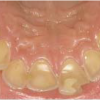

Hamba erosioon

Muu kui katubakterite happe põhjustatud hamba kõvakoe happelist kahjustust nimetatakse erosiooniks. Hape söövitab ehk demineraliseerib hambapinda, muutes selle pehmeks ja nii kiiresti kuluvaks.